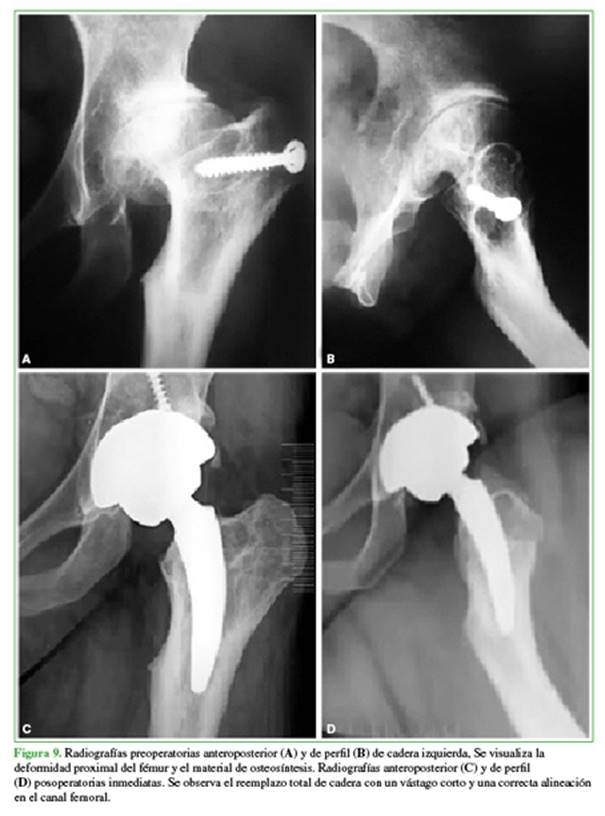

Las deformidades femorales proximales son generalmente una consecuencia de enfermedades del desarrollo de la cadera durante la infancia, fracasos de osteotomías previas o secuelas de fracturas (Figura 9).

Se analizaron prospectivamente 31 pacientes (35 caderas) con deformidades femorales proximales tratados con ATC primaria no cementada utilizando un vástago corto con fijación cervicometafisaria (MiniHipTM). Hubo 19 pacientes masculinos (23 caderas) y 12 femeninos (12 caderas), con un IMC medio de 26,7 ± 4,1 kg/m2. Doce casos (38,7%) tenían un antecedente de procedimiento quirúrgico, y seis de ellos fueron osteotomías infantiles fallidas. La edad media de la serie fue de 44 ± 12 años, el seguimiento medio fue de 81 ± 27 meses y no hubo pérdidas de seguimiento de ningún paciente. Las deformidades femorales proximales se categorizaron de acuerdo con una clasificación de Berry modificada.48 El ángulo cervicodiafisario femoral preoperatorio varió entre 90° y 157°. La discrepancia preoperatoria promedio en la longitud de los miembros inferiores fue de -16,3 mm (rango de -50 a 2). En comparación con la cadera contralateral, la lateralización femoral preoperatoria fue de -7,6 mm en promedio (rango de -28 a 8).

Resultados

A un seguimiento medio de 81 meses, la tasa de supervivencia fue del 97,1% tomando como falla terapéutica a la revisión del vástago por cualquier causa y el 100% tomando al aflojamiento aséptico del componente femoral exclusivamente. No se requirió una osteotomía femoral adicional en ningún caso. El tiempo quirúrgico promedio fue de 66 minutos (rango 45-100). Hubo una mejora significativa en el HHSm al comparar los valores preoperatorios y posoperatorios (47,3 ± 10,6 vs. 92,3 ± 3,7, p = 0,0001).

En cuanto a la evaluación del dolor, el valor medio preoperatorio fue de 8,6 ± 1 y el valor medio posoperatorio fue de 1,1 ± 1,1 (p = 0,0001). La discrepancia de longitud posoperatoria fue, en promedio, de 1 mm (rango de -9 a 18) (p = 0,0001). La lateralización femoral posoperatoria difirió, en promedio, 29 mm (rango de -16 a 20) en comparación con el lado contralateral (p = 0,0001). No se registraron casos de FFPI. No hubo evidencia de osteólisis alrededor de los vástagos femorales. Se observó una radiolucidez del vástago femoral <2mm de ancho, uniforme, en la zona de Gruen 1, sin relevancia clínica.